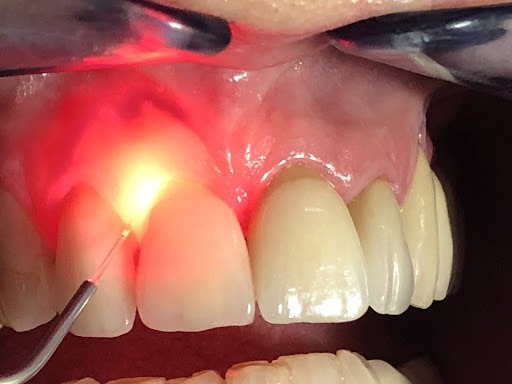

LANAP® (Laser Assisted New Attachment Procedure) is an FDA-cleared laser treatment used to treat moderate to severe periodontal (gum) disease without traditional surgery.

Instead of cutting the gums with a scalpel, LANAP uses a specialized dental laser to:

- Remove infected gum tissue

- Kill harmful bacteria

- Preserve healthy tissue

1. Laser Removal of Infection

A dental laser targets and removes diseased tissue and bacteria deep within the gum pockets.

3. Second Laser Pass

The laser is used again to stimulate clot formation and seal the pocket.